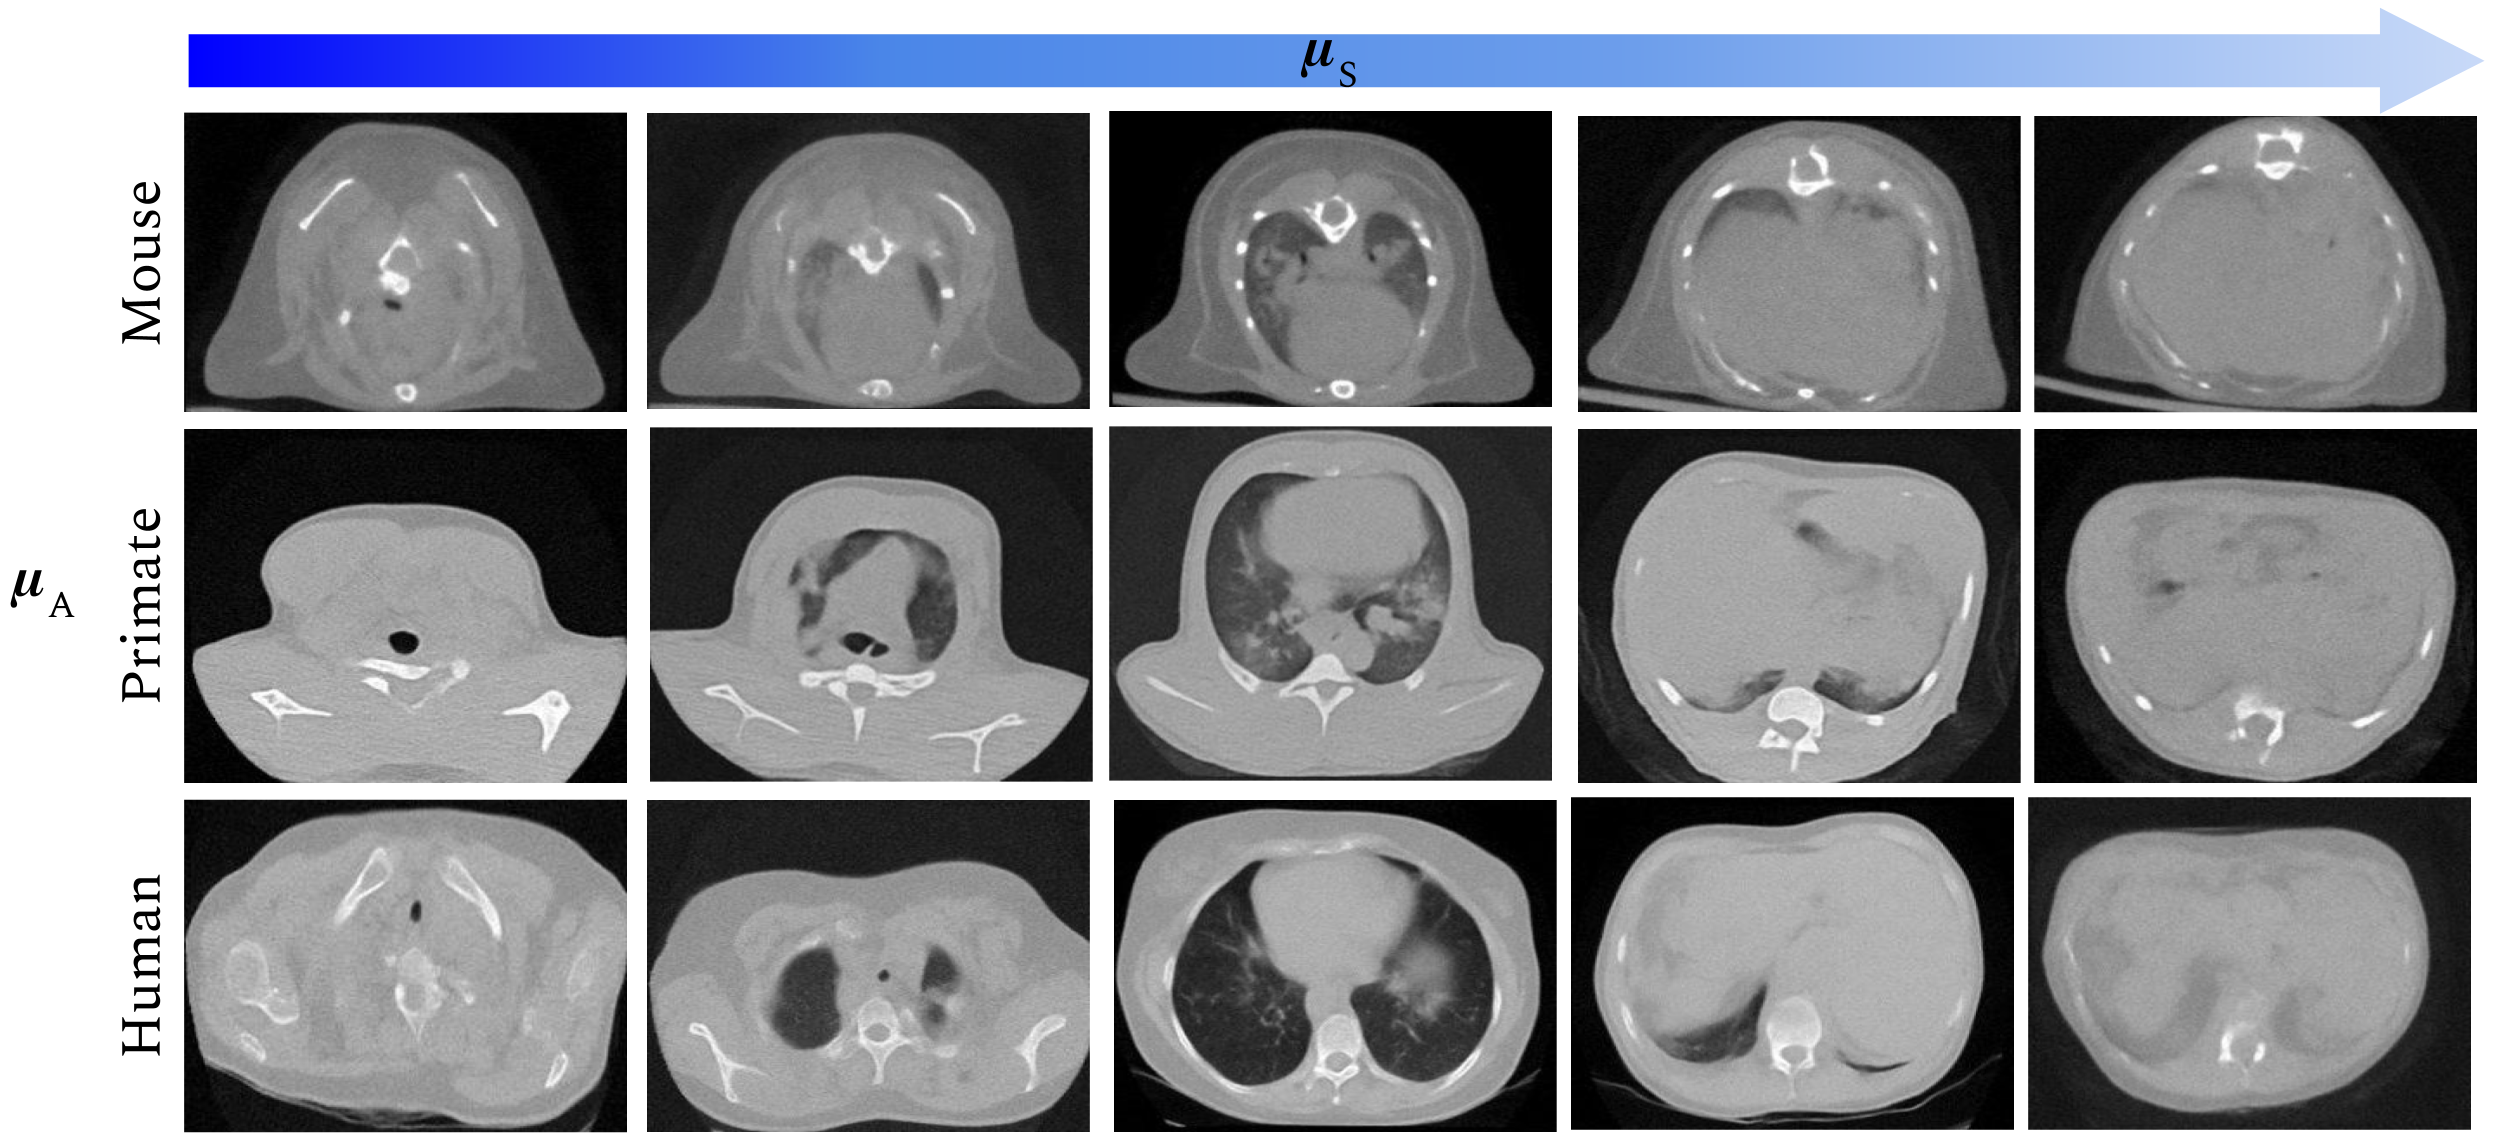

After optimization,

the model can generate realistic images, such as those shown in \figurereffig:generated, by choosing the mean values of , , factors. To illustrate this capacity in \figurereffig:generated, we set a relative slice position of , the animal model is fixed for each row and, the effect of the lung damage variable is modulated from lower to higher in each column.

fig:generated